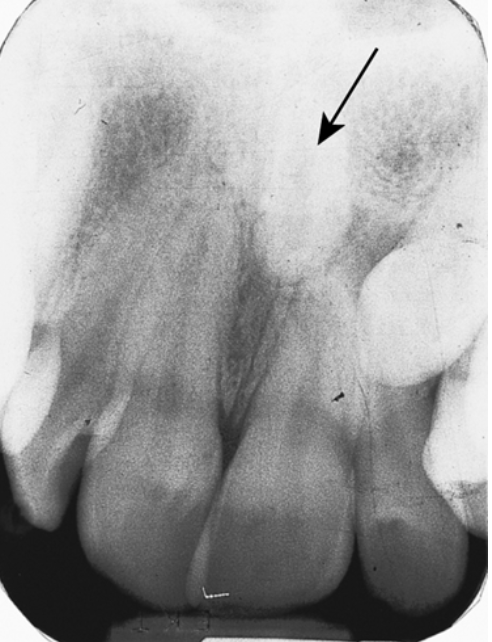

<p>42. What is seen in the radiograph (Fig. 5.28) on tooth #7?</p><p>a. Peg lateral</p><p>b. Dens in dente</p><p>c. Supernumerary tooth</p><p>d. Bifurcated root</p>

42. What is seen in the radiograph (Fig. 5.28) on tooth #7?

b. Dens in dente